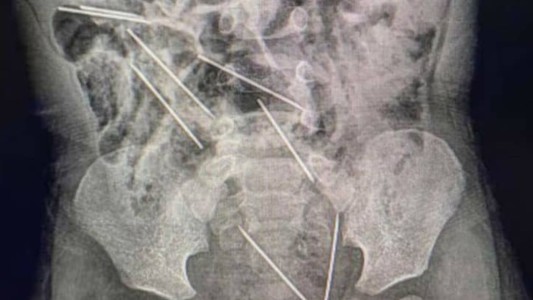

Llevó a su hijo de 2 años con fuertes dolores al hospital y tuvieron que operarlo de urgencia por lo que se había tragado